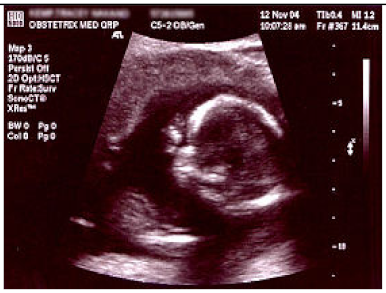

2.6.1. Test Procedure

The stress test involved simulating varying numbers of concurrent users querying the system. For each LLM, we executed 20 clinically relevant prompts, as shown in (Table A2) in the Appendix A. For each VLM, 10 different images with 2 prompts per image resulting in a total of 20 prompts per model were tested. The specific prompts used are listed in (Table A3) in the Appendix A. We tested user loads of 10, 20, 30, 40, 50, 75, 100, 125, and 150 users. In order to measure the robustness of the container as well as the robustness of JAVIS, this experiment queried the JAVIS back-end to measure the complete roundtrip response times. This approach ensured that the test accurately reflected real-world usage scenarios, including the overhead of back-end processing and model orchestration.

JAVIS supports multimodal LLMs or VLMs, allowing the integration of various image types (JPG, PNG, etc.). This enhancement significantly increases the system’s versatility in handling diverse clinical inputs, enabling more comprehensive and accurate patient interactions.